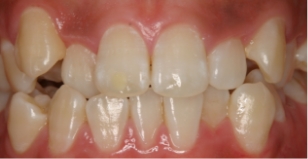

後戻り症例のイメージ

まず皆様に知って頂きたいことは、矯正歯科治療後の歯並びはイメージ写真にあるように後戻りしやすいということです。後戻りの研究で世界的な権威であるR. M. リトル教授によると「現代の矯正治療は悪い歯並びを治す事は出来るが、保定(歯並びを治したのちに、戻らないよう装置を続けること。)をやめてしまうと、大なり小なり後戻りする。」と述べています。

従来の矯正法による後戻りの様子

オランダのジナド先生は従来の矯正法による抜歯矯正治療後の後戻りの様子を、不正咬合を評価する「PARスコア1) 」を用いて報告しました。それによると保定が終了するとその直後から後戻りが始まり、2年後には保定終了から約50%の後戻りがあり、5年後には90%以上の後戻りが生じて、その後も自然な歯並びの変化が続くと報告しています。